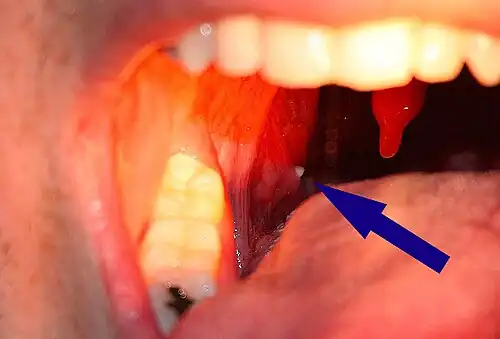

| A tonsillolith lodged in the tonsillar crypt | |

A tonsillolith protrudes from the tonsil -

Large tonsillolith half exposed on tonsil

Closeup of a tonsillolith